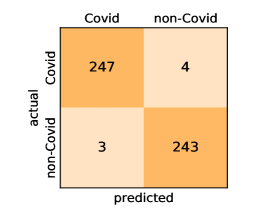

Here, we present and discuss the obtained results for detecting COVID-19 on the considered CT image datasets with different deep networks. We report the quantitative results along with the confusion matrices for every single architecture of the adopted networks.

On the SARS-CoV-2 CT dataset, ResNet101 achieves the best overall performance with respect to almost all evaluation metrics, with an average accuracy and F1-score of and , respectively. The model also achieves an average sensitivity rate of indicating that, on average, only two COVID-19 images are falsely predicted as negatives. It is also powerful enough to correctly identify all Non-COVID-19 cases with only one false positive resulting a specificity rate of . The highest sensitivity score of is achieved by the InceptionV3 model, where only one COVID-19 image is falsely predicted as negative on average. The SqueezeNet model obtains the lowest performance with respect to all evaluation metrics with a fairly acceptable average accuracy and sensitivity scores of and , respectively. Also the ShuffleNet architecture obtains satisfactory performance with approximately improvements on average for all metrics compared with SqueezeNet. Although the results obtained by these models are inferior compared with the rest of models, but they are more efficient. This matches their main objective of reducing the computational costs rather than improving their visual recognition abilities. The rest of models achieve competitive performance and very promising results with slight performance differences. Comparing the different variants of ResNet and DenseNet, we can see that the deeper variants from each architecture yield a slightly better performance. The deeper ResNet101 and ResNeXt101 show a marginal gain in performance compared with their shallower counterparts. The details about class-wise results for each model are summarized in the confusion matrices in Figure 9.

Our models achieve fairly good performance compared with the recently published work using the exact network architectures. This can bet attributed to a better optimization of our models and the effectiveness of our fine-tuning strategy using custom-sized inputs determined specifically for each architecture. Here, we see that DenseNet201 outperforms all other architectures. The model achieves average accuracy and sensitivity scores of and , respectively. It also identifies all COVID-19 images with only four images, on the average, are falsely predicted as Non-COVID-19. DenseNet169 achieves the second best average accuracy of and a very high sensitivity identical to the best model. The DenseNet121 and Xception models have nearly identical results for all evaluation metrics. We observe that small-sized networks such as ResNet18 achieves comparable results with other deeper models. The SqueezeNet and ShuffleNet models perform at a similar level of accuracy. The variants of the ResNeXt models have comparable results and perform as good as the different ResNet variants. A detailed analysis on the class-wise results for individual models is presented in the confusion matrices in Figure 10.